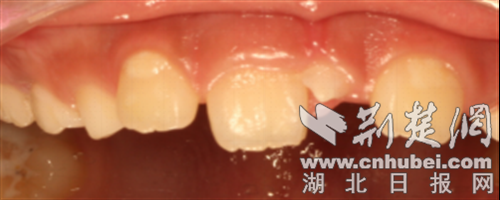

一颗乳牙迟迟未脱落。 通讯员 供图

它的“存在感”可强可弱:有的多生牙会像正常牙齿一样萌出,肉眼就能看到;有的则一直埋伏在颌骨内,只有拍X光片(如口腔CT)时才会被发现。从形态上看,它也很“任性”——可能是正常的牙齿形状,也可能是畸形的小颗粒,颜色、大小都与正常牙齿有明显差异。

挤占正常牙齿空间:导致恒牙萌出位置异常,出现牙齿排列拥挤、不齐。